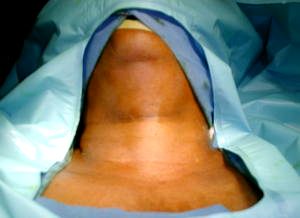

Cervicotomia transversa

Figura 1 -

Posición de cervicotomia anterior, con extensión cervical y anestesia general.

• Observe la cicatriz de la cervicotomia anterior en la base del cuello.

• Se realiza cervicotomia amplia anterior baja, sobre la cicatriz de la cervicotomia anterior.